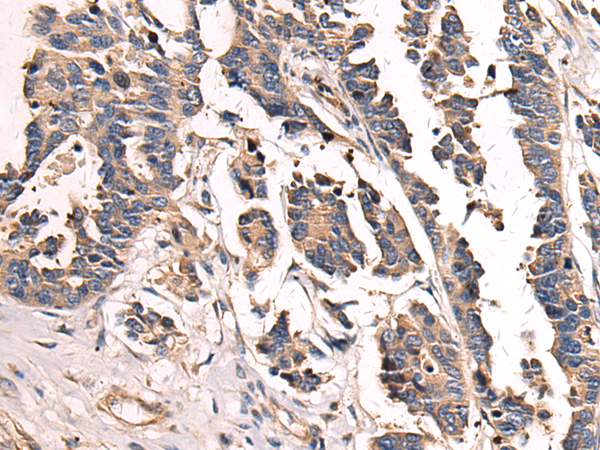

The image is immunohistochemistry of paraffin-embedded Human colorectal cancer tissue using P03323(SH3BGR Antibody) at dilution 1/70. (Original magnification: ×200) |